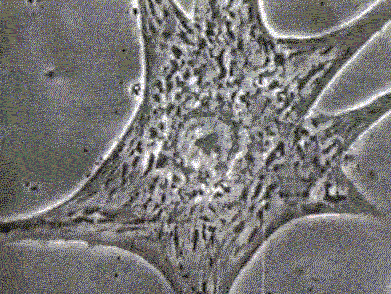

11.

跳动的心脏细胞

体外培养的心肌细胞经常会出现自发搏动现象,且同一个培养皿中的心肌细胞的搏动往往还是同步的,因而把心肌细胞作为中胚层分化的指示细胞,来衡量多能干细胞分化为中胚层的潜力。